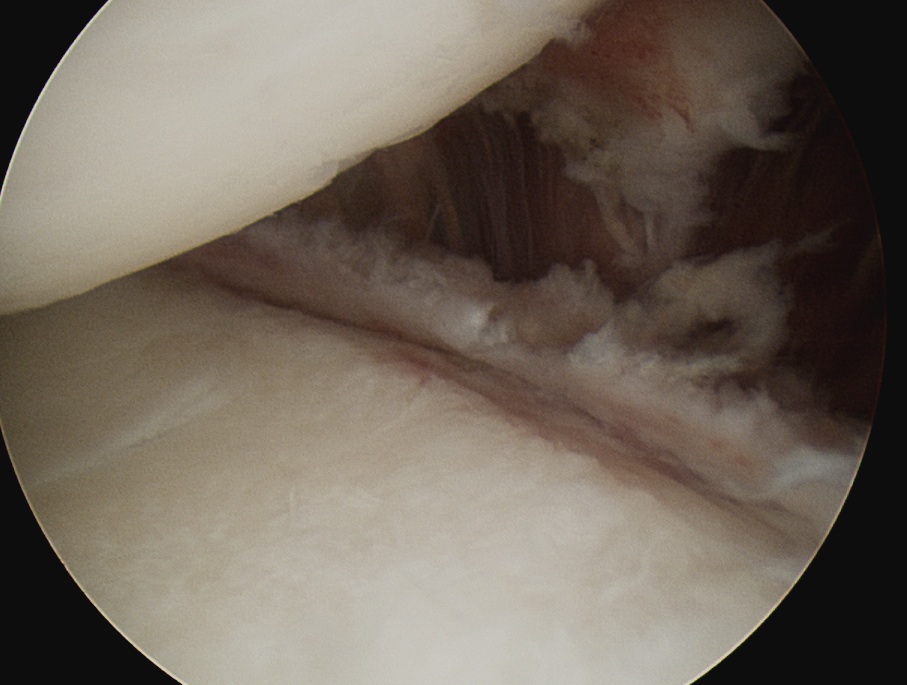

Rotator interval release

Release anterior IGHL